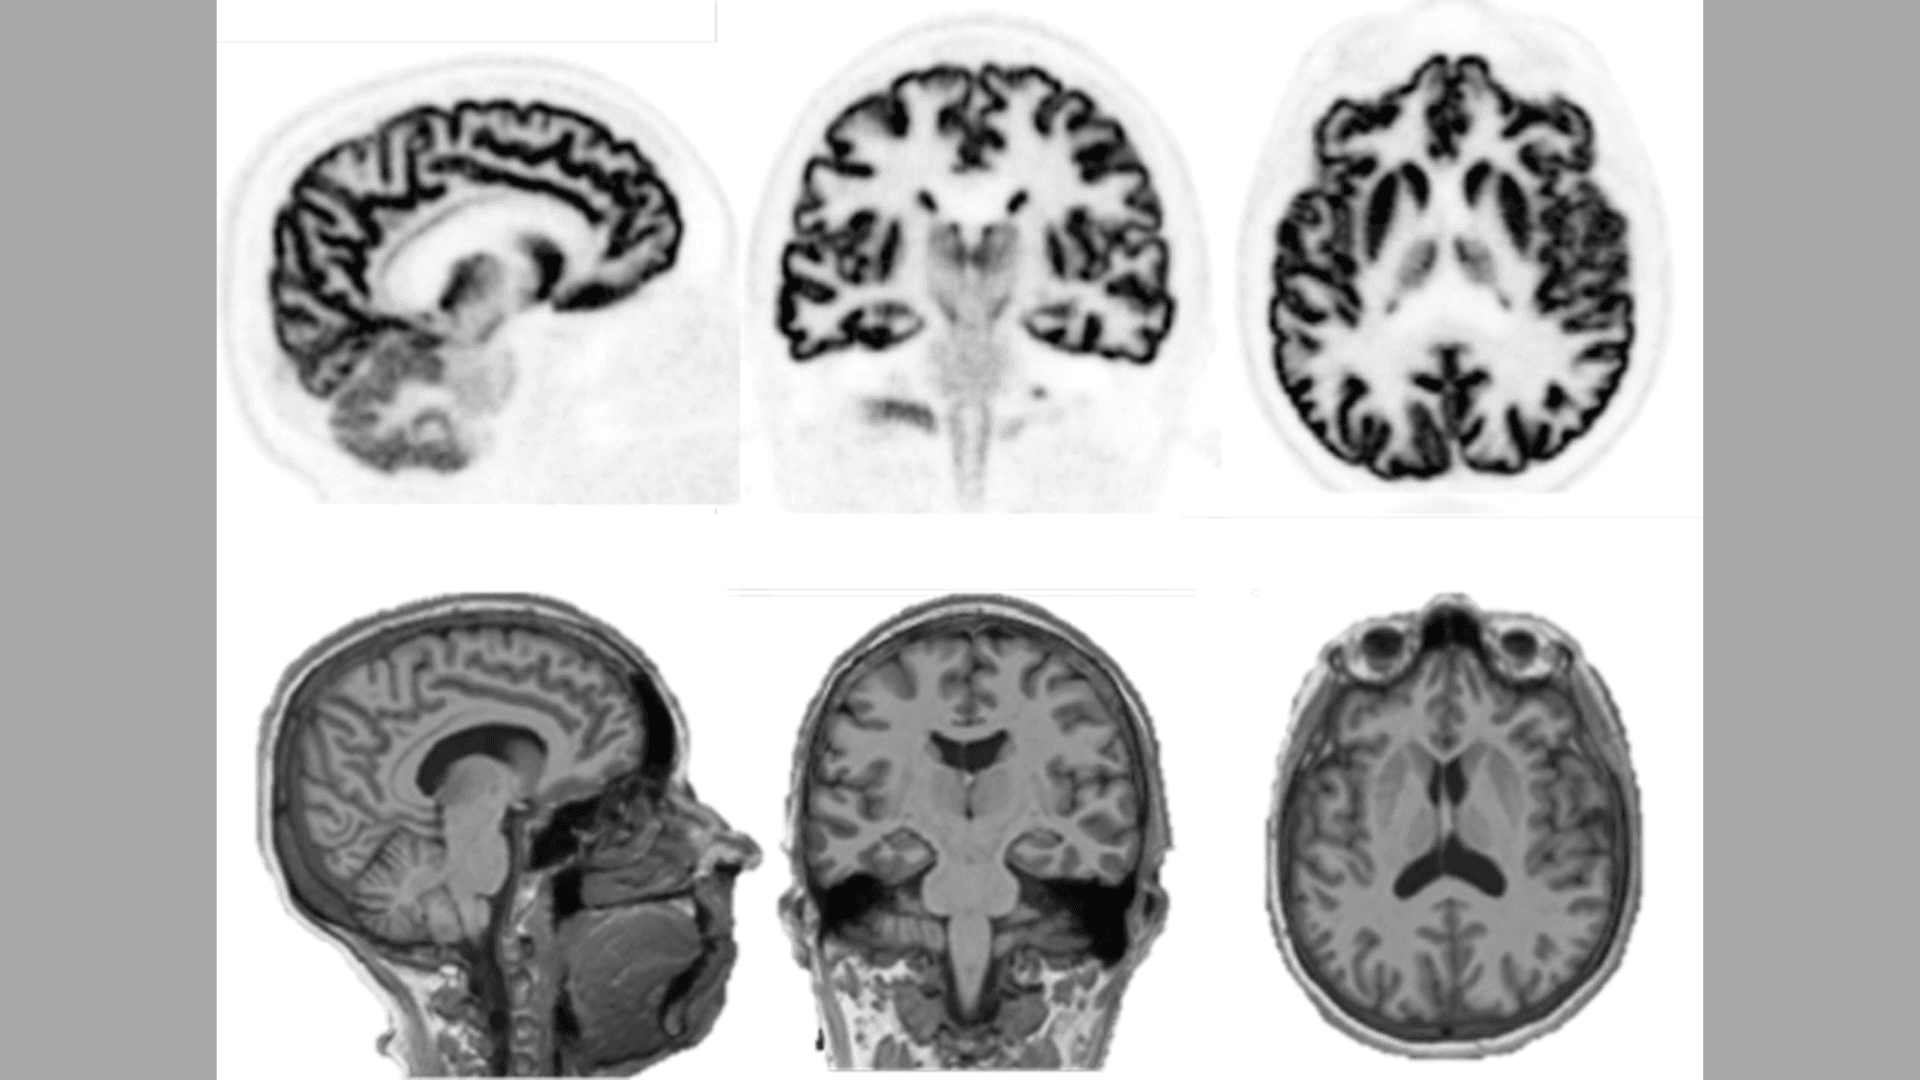

PET, farmakokinetik ölçümler ve nöroreseptör aktivitelerinin izlenmesinde kullanılarak daha ayrıntılı ve özelleştirilmiş tıbbi çözümler sunar. İlaç geliştirme alanında da önemli bir araç olarak kabul edilir. Beyin görüntüleme cihazları, nöroinflamasyon ve nörolojik hastalıkların biyokimyası üzerine önemli bilgiler sunar.